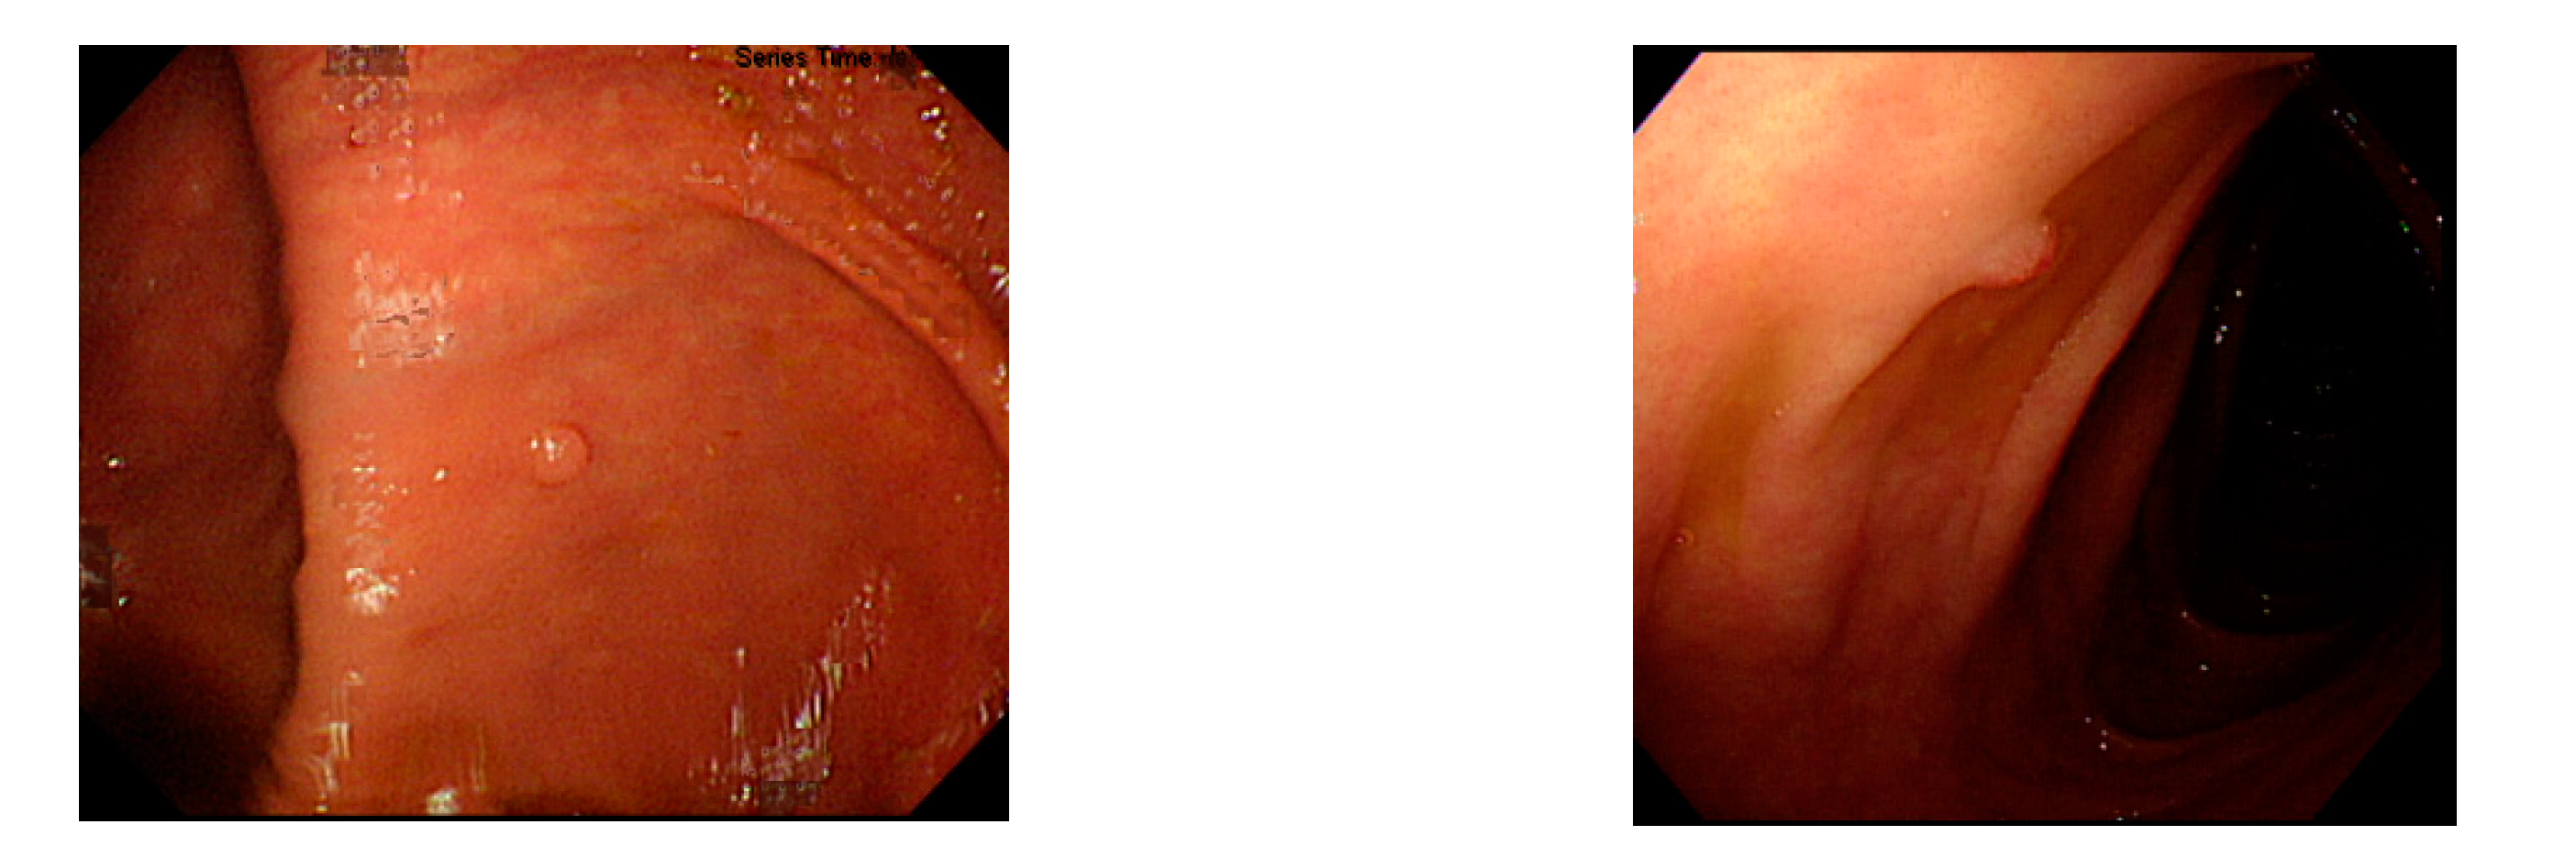

Figure 2. Excessive intestinal wall textures with small polyps.

Currently, many medical images are processed into grayscale images, such as ultrasound, computed tomography (CT), and magnetic resonance (MR) images. Tan et al. [44] applied a gray-level cooccurrence matrix and CNN to CT images for polyp diagnosis. Zhang et al. [45] compress the three-channel color images of chest CT to grayscale images. A five-layer deep CNN with stochastic pooling is used to diagnose chest-based COVID-19. Xie et al. [46] mentioned that in deep learning, colors are not the key features influencing accurate image classification. They also discovered that in X-ray image classification, the speed and accuracy of processing grayscale images were considerably higher than those of processing RGB images. The grayscale method used was ITU-R Recommendation BT.601 [47]. Moreover, misjudgments were easily made in the presence of excessive intestinal wall textures, when polyps were too small (Figure 2), and when polyp textures were similar (Figure 3) to intestinal wall textures.